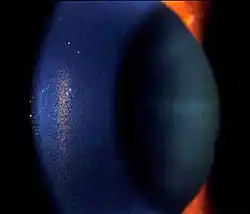

| Slit lamp photograph showing Krukenberg's Spindle as pigment cell deposits on the cornea | |

Krukenberg's spindle is the name given to the pattern formed on the inner surface of the cornea by pigmented iris cells that are shed during the mechanical rubbing of posterior pigment layer of the iris with the zonules that are deposited as a result of the currents of the aqueous humor. The sign was described in 1899 by Friedrich Ernst Krukenberg (1871-1946), who was a German pathologist specialising in ophthalmology.[1]